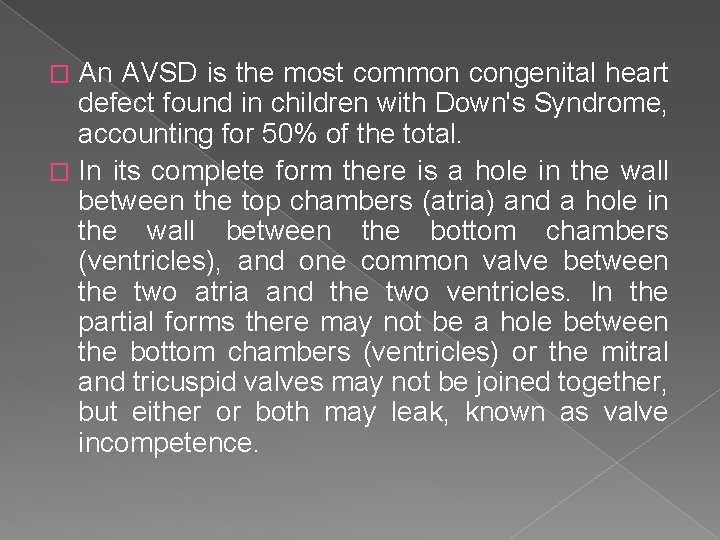

� Endocardial cushion defect is also called atrioventricular septal defect (AVSD). AVSD involves problems with the structure of the heart. The heart normally has 2 upper chambers (atria) and 2 lower chambers (ventricles). A normal heart also has 2 heart valves (the tricuspid and mitral valves) that separate the upper and lower chambers.

An AVSD is the most common congenital heart defect found in children with Down's Syndrome, accounting for 50% of the total. � In its complete form there is a hole in the wall between the top chambers (atria) and a hole in the wall between the bottom chambers (ventricles), and one common valve between the two atria and the two ventricles. In the partial forms there may not be a hole between the bottom chambers (ventricles) or the mitral and tricuspid valves may not be joined together, but either or both may leak, known as valve incompetence. �